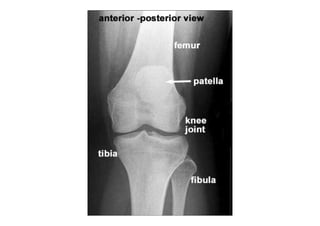

• Radiografia do joelho